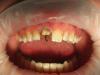

iFinn Опубликовано 24 марта, 2013 Поделиться Опубликовано 24 марта, 2013 (изменено) Навеяло темой от Art7...Только у моей пациентки места было меньше, полноценной вкладки-коронки не вышло. Вышел штифтовый зуб (дц+облицовка).Готовая работа- это только две последние фотографии, третяя-четвертая с конца- времяшка. Изменено 24 марта, 2013 пользователем iFinn Ссылка на комментарий

iFinn Опубликовано 26 марта, 2013 Автор Поделиться Опубликовано 26 марта, 2013 а я вот не пойму, почему там не сделать вкв и коронку? у меня такие на "ура" делаются =) на вашем внимке, так это ваще идеал для вкв )))Я бы тоже так сделал (вкладка+коронка), но там по прикусу места очень мало, и то и то не влезло бы. Только поэтому пошел на подобную конструкцию. Могу вечером фото в прикусе добавить, просто сейчас с телефона сижу. Ссылка на комментарий

iFinn Опубликовано 26 марта, 2013 Автор Поделиться Опубликовано 26 марта, 2013 ну поидее, вы снимаете оттиск под вкв в вашей ситуации, а техник уже всё подгоняет по прикусу так, чтобы потом и коронка стала.У пациентки глубокое резцовое перекрытие, плюс сама толщина центральных резцов небольшая. Если редуцировать вкладку под коронку с небной поверхности, а потом еще с вестибулярной (ну, чтобы глубину цвета дать и естественность), то от вкладки ничего не останется. Ссылка на комментарий

iFinn Опубликовано 26 марта, 2013 Автор Поделиться Опубликовано 26 марта, 2013 Мне кажется результат который вы получили штифтовым зубом можно было получить и через классический вариант, вкладка+коронкаНа штифтовом зубе, который получился, небная поверхность-голый циркон, при этом зуб уже в прикусе и резцовом ведении, при этом толщина циркониевой культи-тонкая, при этом техник очень жаловался на то, что места для работы с керамикой у него совсем впритык, там еще цвет сложный, нужна глубина. Я не знаю, может просто мои фотографии недостаточно информативны, да и мне еще учиться и учиться... С уважением. на 15 свищевой ход??Да, только это не 1.5, а 5.5. 1.5, как и 2.5 отсутствуют как класс.Если честно, то 1.1 это далеко не все проблемы пациентки, но, как это часто бывает, беспокоят только видимые глазу.Упреждая следующий вопрос. После беседы со мной пациентка в курсе большинства своих проблем в области зубо-челюстной системы, ушла собираться с мыслями/силами, для дальнейших свершений. Ссылка на комментарий